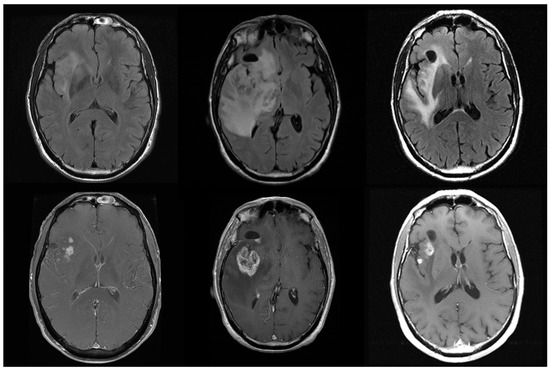

- Kebir, S.; Rauschenbach, L.; Gielen, G.H.; Schafer, N.; Tzaridis, T.; Scheffler, B.; Giordano, F.A.; Lazaridis, L.; Herrlinger, U.; Glas, M. Recurrent pseudoprogression in isocitrate dehydrogenase 1 mutant glioblastoma. J. Clin. Neurosci. Off. J. Neurosurg. Soc. Australas 2018, 53, 255–258. [Google Scholar] [CrossRef] [PubMed]